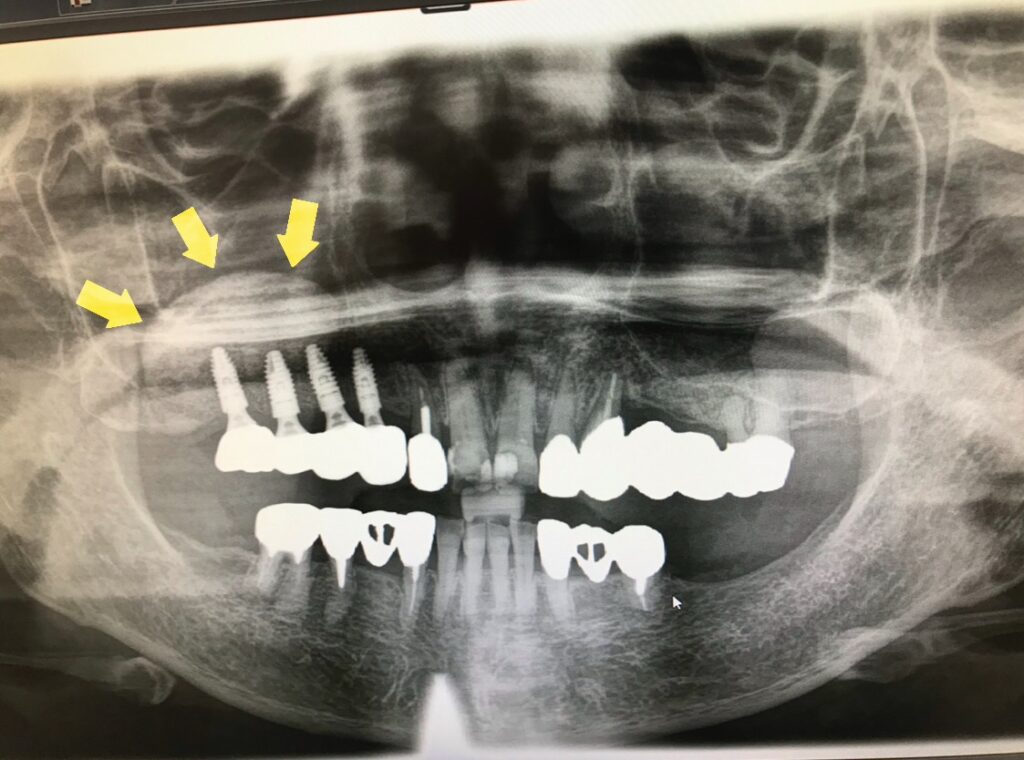

40代女性② インプラントに必要な骨を造成した症例

骨がなくインプラント治療を諦めいてた患者さんに対して、CT画像の通り、インプラントを入れるための骨を造りました(黄色い矢印⇨)。比較として、歯が無い状態を放置していると、骨が吸収し、骨が薄くなっています(赤い矢印⇨)。

| 施術名 | サイナスリフト(骨造成) |

| 治療期間 | 約6ヶ月 |

| 費用 | 骨造成費 15万円(当院価格) |

| リスクや副作用 | 蓄膿症など鼻の疾患がある場合は、適さない場合がある。術直後は、痛み・腫れ・違和感・鼻出血が発生する場合がある。上顎洞に炎症が波及し、上顎洞炎を起こすことがある。 |